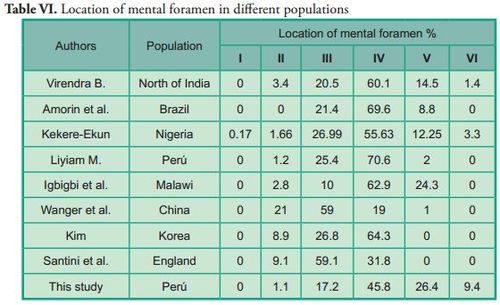

Several authors have studied the location of the mental foramen using the longitudinal axes of teeth as reference. However, there were variations in the results, which could be attributed to ethnic differences (Table VI).

Several authors have studied the location of the mental foramen using the longitudinal axes of teeth as reference. However, there were variations in the results, which could be attributed to ethnic differences (Table VI).